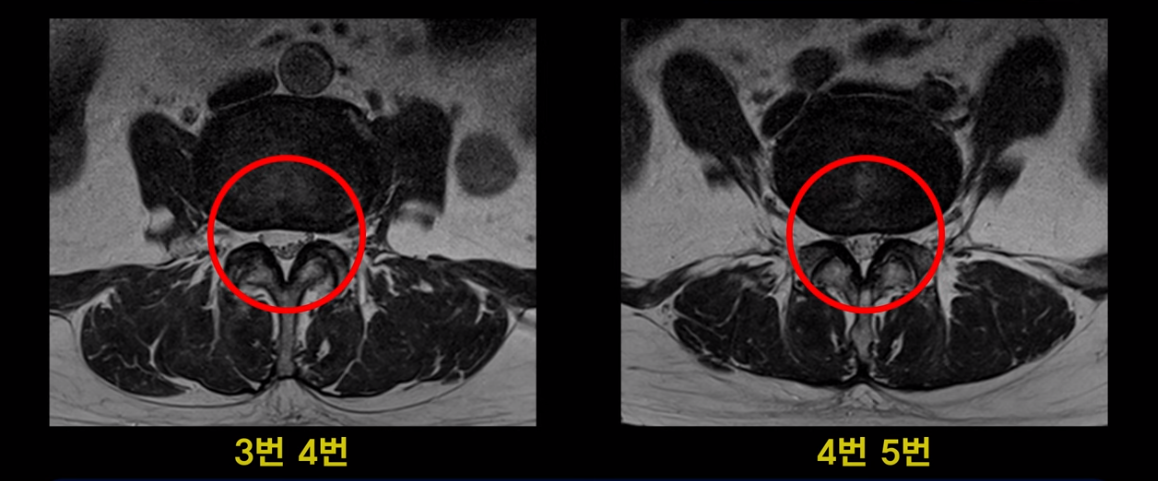

3번 4번과 4번 5번에 중심성 협착이 있는데

4번 5번이 더 심합니다.

또 4번 5번 마디에 오른쪽으로 찢어져서 밀려나온 디스크 탈출이 보입니다.